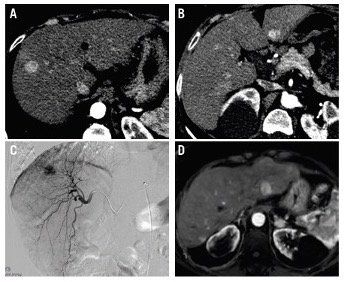

Figure 1. Arterial phase CT scan shows 2 nodules located in segment 8 and 2, the biggest one with a 13-mm diameter. (A & B). Right hepatic lobe DSA depicts the hypervascular tumor and DEB-TACE was performed in a super-selective way. (C) In the 42 months post OLT, MRI showed (T1+Gd FatSat arterial phase) multiple hypervascular hepatic nodules (arrows) and a left adrenal metastasis (arrowhead) were documented. (D)

A 64-year-old white woman with hepatitis C virus (HCV) infection-related well-compensated cirrhosis (Child-Pugh score, B7; Model for End-stage Liver Disease, 12 points) was diagnosed with hepatocellular carcinoma (HCC) within the Milan criteria (bilobar disease, 2 nodules, largest diameter of 13 mm) (Figure 1). The patient’s performance status was optimal, without ascites and no associated diseases. She was cataloged as stage A according to the Barcelona Clinic Liver Cancer staging system and received an orthotopic liver transplant (OLT).

Serum alpha-fetoprotein (AFP) level at diagnosis was 16.6 IU/mL (19.6 ng/mL). The patient received 2 cycles of doxirubicin-loaded drug-eluting beads transarterial chemioembolization (DEB-TACE) with 75 to 150 micron particles as bridging therapy. The right lobe was initially treated followed by a second session in the left lobe. Both sessions were performed within a 3-month period. A computed tomography (CT) scan after the first procedure showed a complete tumor response (with modified response evaluation criteria in solid tumors [mRECIST] criteria) while a radiologic evaluation after the second session was not possible as the patient was transplanted less than a month after the procedure. No surgical or medical complications were reported and the patient recovered satisfactorily and was discharged on day 12 post surgery.